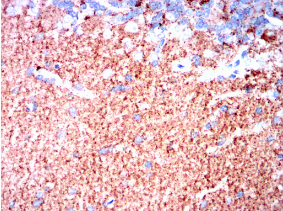

SYT1 Mouse Monoclonal antibody[8G11]

SYT1: synaptotagmin I. The synaptotagmins are integral membrane proteins of synaptic vesicles thought to serve as Ca(2+) sensors in the process of vesicular trafficking and exocytosis. Calcium binding to synaptotagmin I participates in triggering neurotransmitter release at the synapse.

IHC    1/200 - 1/1000